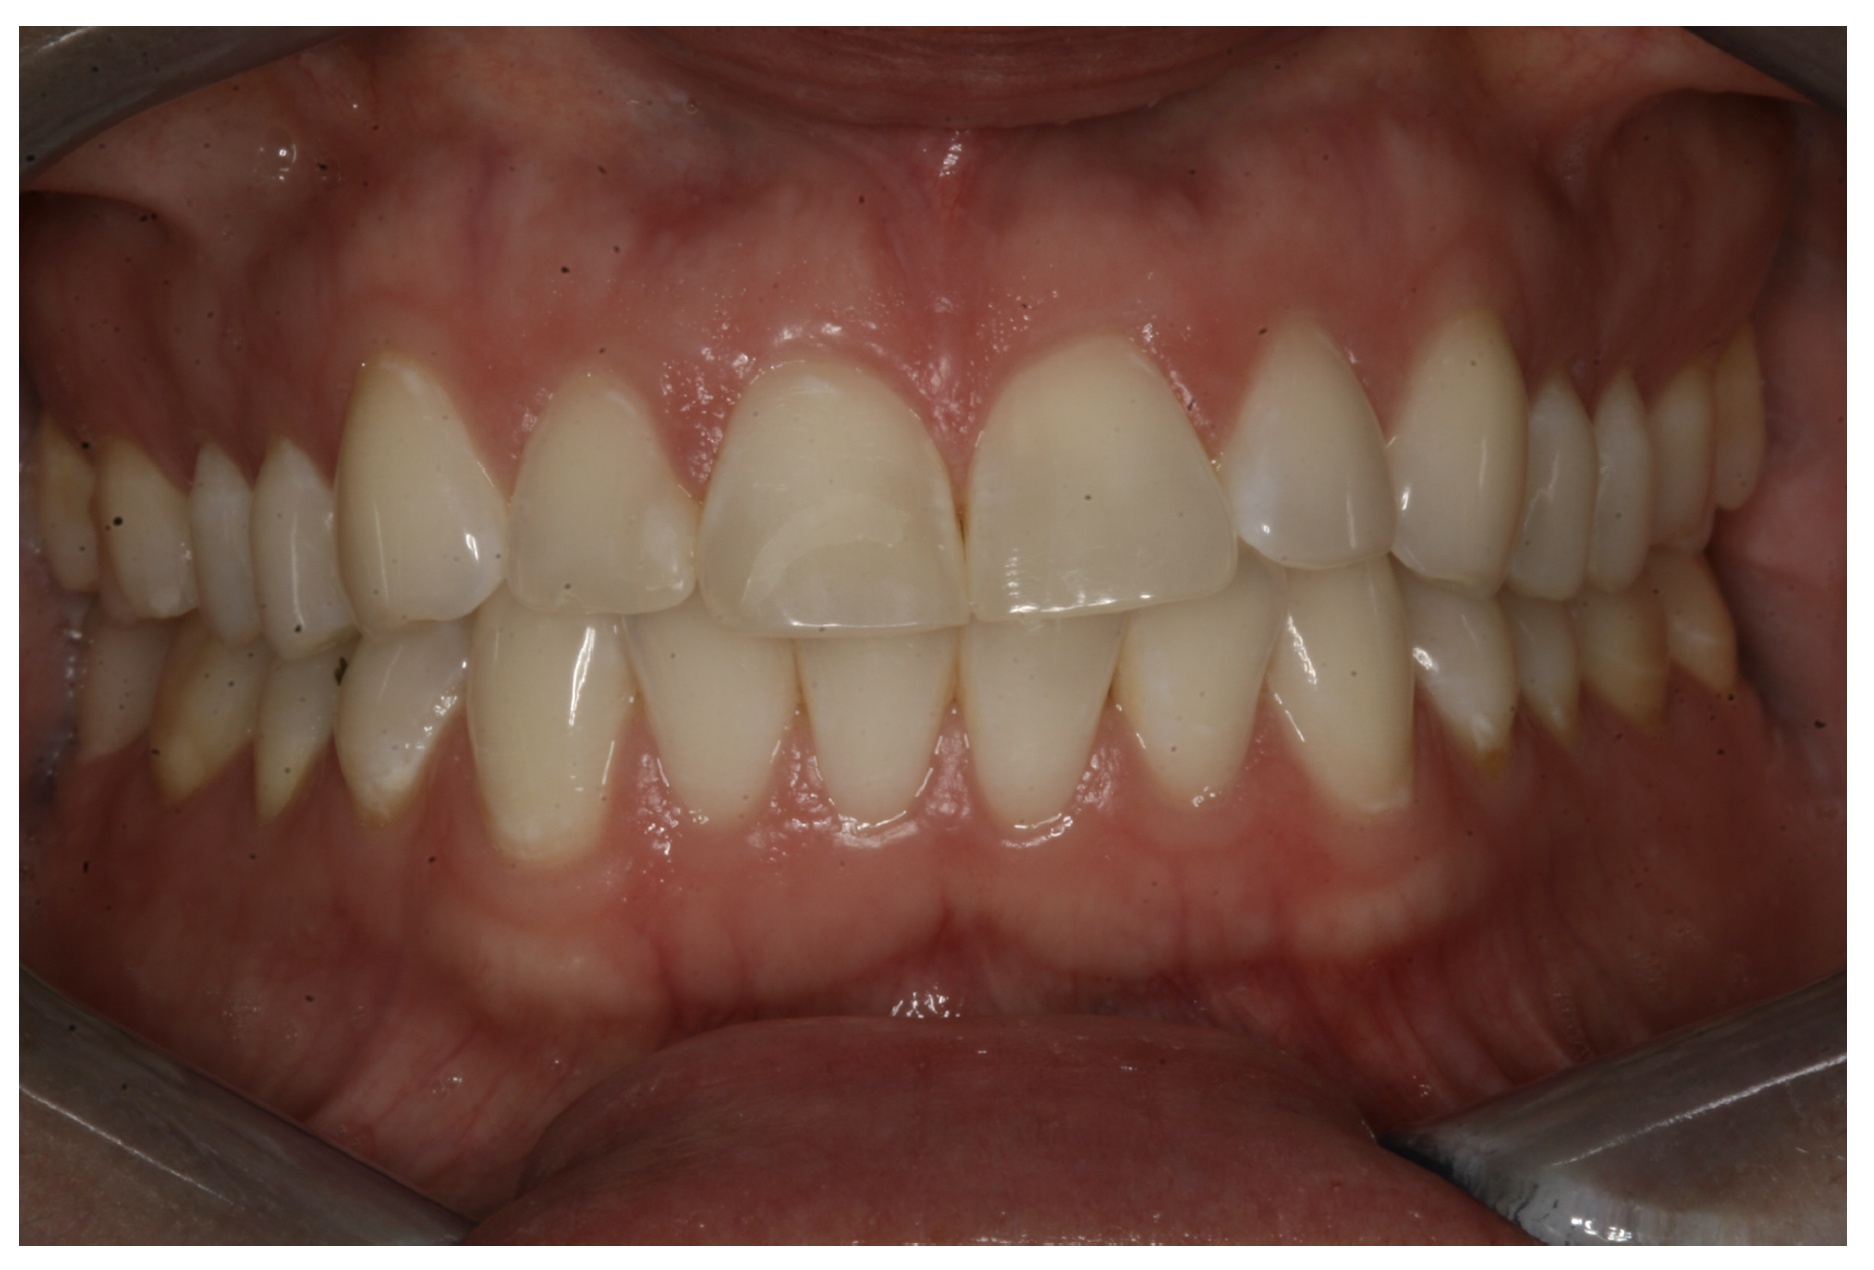

For the case in Figure 9 through Figure 11, the patent presented for an initial consultation with bonding completed on teeth Nos. 7 through 10 a few years prior with a chief complaint of not liking the way the resin bonding looked and how it was wearing. Up to this point, the bonding had repeatedly chipped and been repaired three times already. The patient's canines also exhibited signs of incised wear and flattening, which she did not like. Based on the patient's goals for her smile and her financial budget, she elected to have porcelain veneers completed on teeth Nos. 6 through 11. The total esthetics of the case design were somewhat limited given that the patient's esthetic zone included her posterior teeth and mandibular anterior teeth. Therefore, the color and characteristics of the veneers had to match her existing dentition closely.